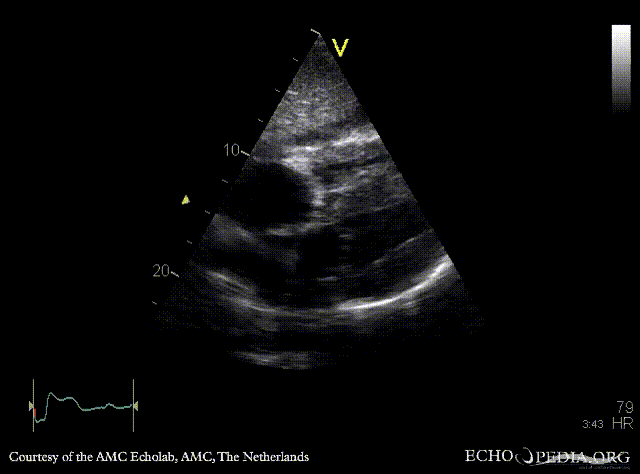

Amyloidosis

PLAX: concentric left ventricle hypertrophy in a patient with amyloidosis PSAX: concentric left and right ventricle hypertrophy